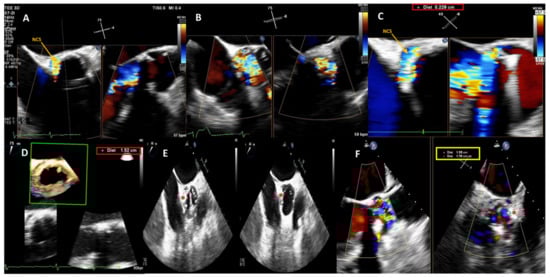

Figure 1.

Baseline 2D/3D Transesophageal Echocardiogram (TEE) color Doppler showing a 15 × 2.3 mm large crescent-shaped NCS paravalvular leak with severe regurgitant jet (A–C) and 3D TEE color Doppler showing the PVL dimensions and location (D). Post-procedure 2D TEE color Doppler showing the correct position of the device (red star) during the cardiac cycle (diastolic and systolic frames, respectively) (E) and confirming stability of the 14 × 6 mm rectangular waist PLD (red star) without impingement on the mechanical prosthetic aortic valve (F). NCS, non-coronary sinus; PLD, Occlutech Paravalvular Leak device.